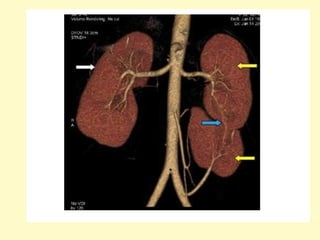

Incomplete duplicated collecting system, coronal maximum intensity

projection (a) and volume rendering (b) show an incompletely

duplicated left pyelocalyceal system and ureter, the left ureters

converge and fuse near the bladder